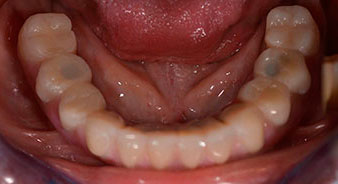

Tras explicarle las distintas opciones de tratamiento, la paciente se decidió por la extracción de la dentición residual en el maxilar inferior, la implantación inmediata y el tratamiento con el método Fast & Fixed (bredent medical), con el que la prótesis dental fijada provisionalmente se atornilla sobre cuatro implantes en el mismo día de la intervención. El objetivo era operar a la paciente el viernes para que el lunes pudiera tomar parte en los exámenes orales para la prueba de acceso a la universidad.

Para la planificación y la minimización del riesgo, se realizó una tomografía volumétrica tridimensional (TVD, Planmeca) que mostró que la calidad y la cantidad del tejido óseo era suficiente para la intervención quirúrgica y el tratamiento inmediato con el método Fast & Fixed. Siguiendo el protocolo de este método, se insertaron los implantes en la región de las piezas 35, 32, 42 y 45. Debido a la inclinación de hasta 45 grados de los implantes distales, el perfil de emergencia se desplazó hacia posterior y se generó un mayor polígono de soporte (fig. 3).